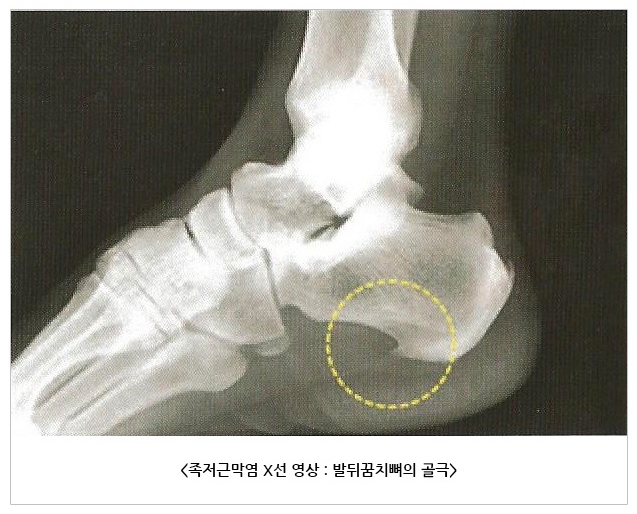

신체 검진 외에 추가적인 검사가 반드시 필요한 경우는 흔치 않습니다. 그러나 증상이 전형적인 족저근막염의 양상이 아니거나 적절한 치료에도 증상 호전이 없는 경우 다른 질환과의 감별을 위해 방사선 검사, 근전도 검사 등을 시행하기도 합니다.